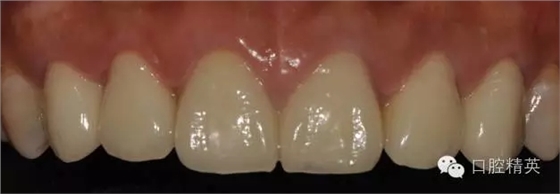

修復體完成口內(nèi)照片

修復體完成后正面觀